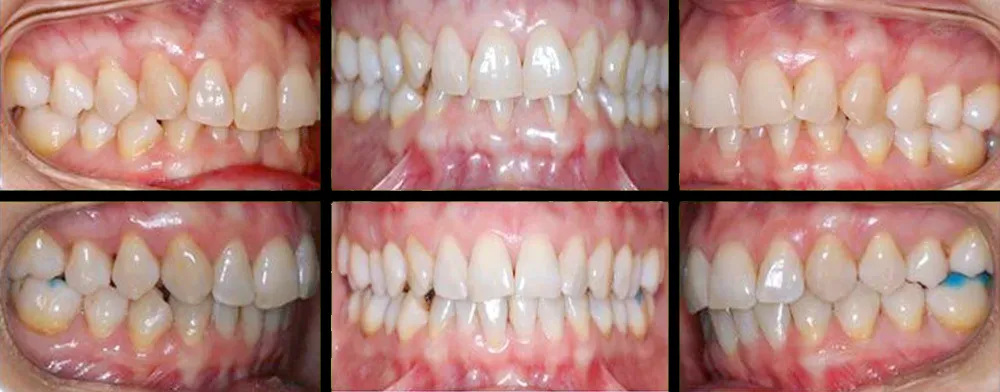

En clínica dental María Jiménez somos especialistas en ortodoncias, siendo la especialidad que se encarga del correcto posicionamiento de los dientes en la boca, para una óptima función masticatoria, fonética y estética, evitando muchos problemas debidos al apiñamiento y mal posición de los dientes.

Tener los dientes alineados y una buena oclusión generan un buen estado de salud bucal y evita problemas en el futuro además de una estética y una sonrisa más atractiva. Las mal oclusiones afectan el estado de la boca, pero además causan otros problemas dentales como desgastes en los dientes, problemas de encías, fracturas, y dificultad muchas veces para poder llevar una buena higiene dental.

Con los tratamientos de ortodoncia conseguimos muchos beneficios a nivel de higiene, estética, salud dental y evitamos futuros problemas funcionales, mejoramos muchas veces la autoestima de los adolescentes y la salud bucal en general.